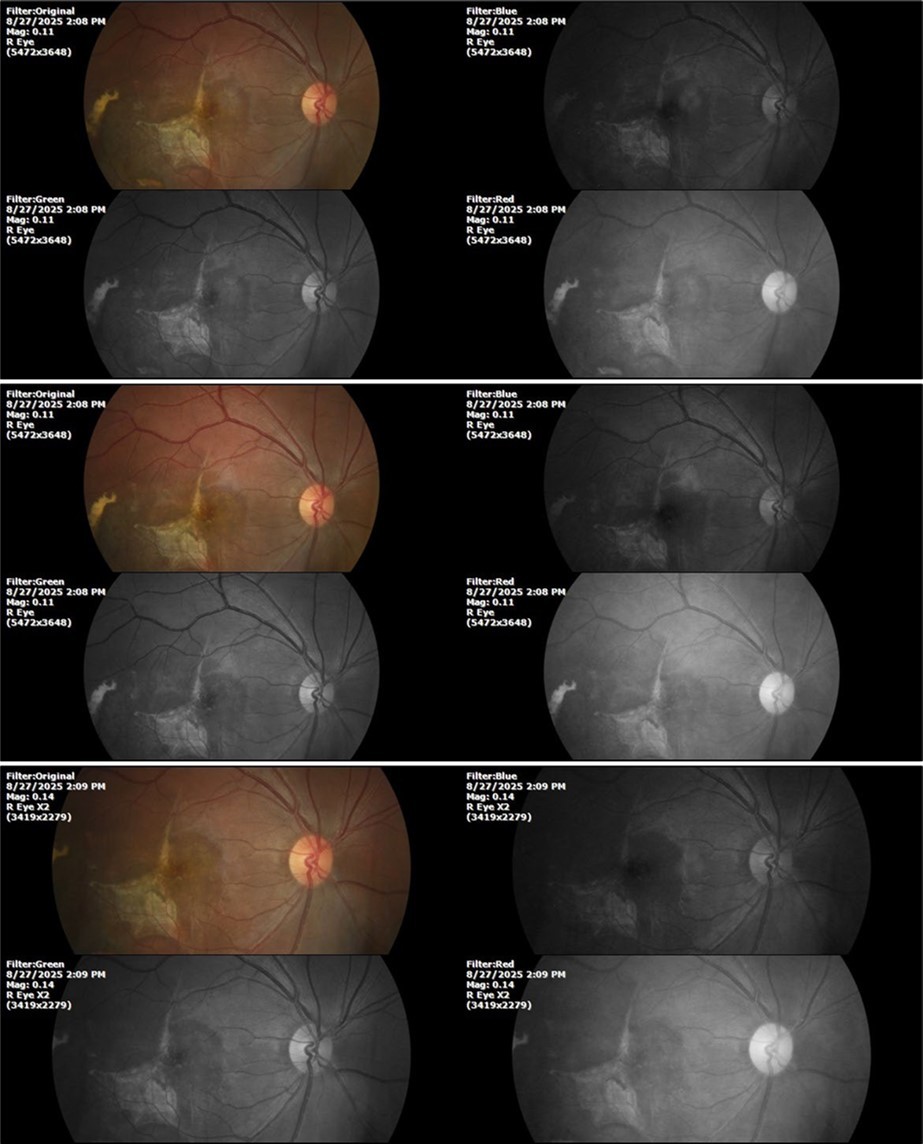

Figure 8.The photograph of the superior temporal region of the retina of the right eye shows the extent of subretinal bleeding as well as retinal edema.

Figure 9.The extent of bleeding, mainly subretinal, is extensive and of significant volume, suggesting choroid rupture in this area.

Figure 10.The location of the bleeding is mainly subretinal, although blood is seen in minimal quantity in the vitreous body.

Figure 33.The 3 previous photographs show that whitish mass has almost completely disappeared, and to date only a remnant remains on the left side of the photograph. The chorioretinal scar that is now observed corresponds to the area affected by the blunt trauma, which presumably caused rupture of Bruch's membrane. Fortunately, the macular region has recovered almost in its entirety, so the impairment in central vision was minimal.